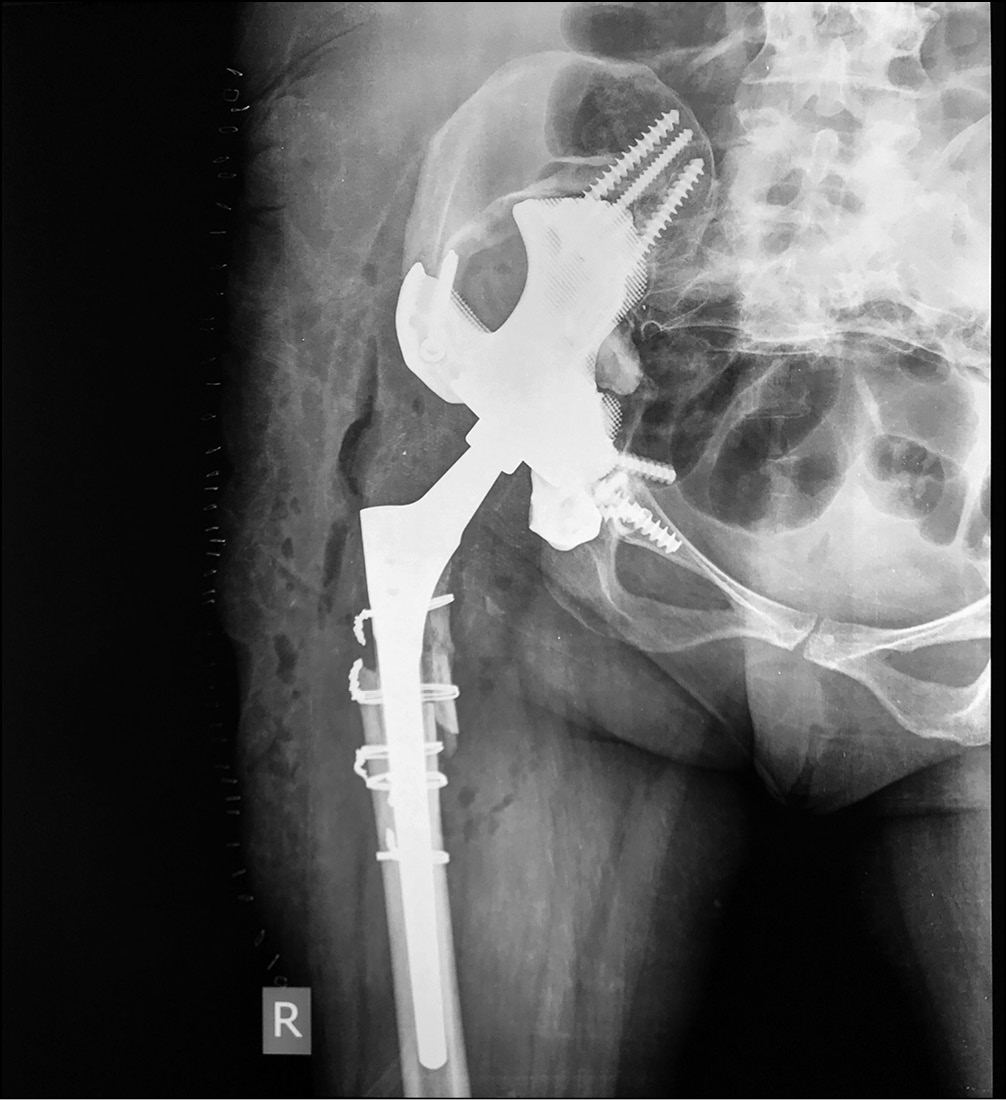

Операцию выполняли в положении больной лежа на здоровом боку с использованием прямого бокового доступа. Удалили рубцово-измененные ткани. При удалении бедренного компонента произошел перелом бедренной кости. Вертлужный компонент с остатками костного цемента удалили без технических трудностей. Выполнили анатомическую установку индивидуальной 3D-конструкции согласно предоперационному планированию и фиксацию 7 винтами.

В полусферическую часть 3D-имплантата установили ацетабулярный компонент цементной фиксации двойной мобильности Novae Stick 45 мм. Проксимальный фрагмент бедренной кости, сломанный при удалении бедренного компонента, фиксировали 5 серкляжными швами и в бедренную кость имплантировали ревизионный бедренный компонент Wagner SL 190/14 (рис. 14).

Рис. 14. Рентгенограмма после операции: достигнута прочная первичная фиксация имплантата в кости, восстановлено анатомическое положение вертлужной впадины